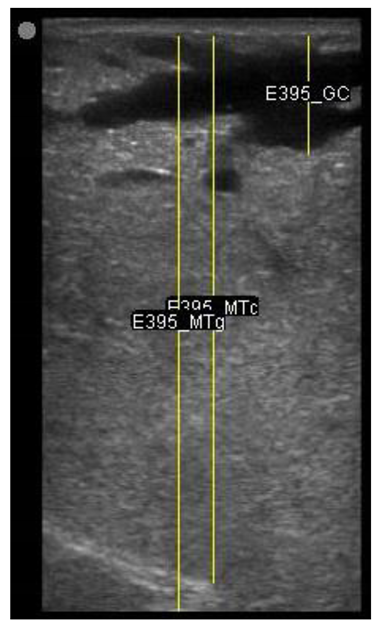

| 109 days of pregnancy (P109) Scanning depth 4.7 cm | ![]() | ![]() | MT generous: 36.8 mm MT conservative: 27.2 mm Gland cistern: 4.7 mm Parenchyma: 15.4 mm Fat Pad: 5.5 mm |